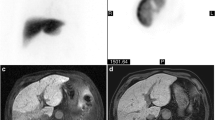

The baseline characteristics of the patients are shown in Table 1. Of the 69 patients, 31 were men and 38 were women, with a median age at diagnosis of 57.0 years. Among the 16 patients who died or underwent liver transplantation, 6 received transplantation. Liver transplantation was performed assuming that the patient would have died without it. The mean time from admission to Tc-99m GSA scintigraphy in this study was 2.4 (standard deviation, 0.93) days. The median (interquartile range) values for LHL15 and HH15 were 0.826 (0.725–0.876) and 0.768 (0.705–0.817), respectively. Typical Tc-99m GSA scintigraphy images of a patient without SLI with a normal LHL15 value and those of SLI patients are shown in Supplementary Fig. S1.

Next, the LHL15 values of patients who died or underwent liver transplantation were compared with those of patients who survived (Fig. 2). We also examined Tc-99m GSA scintigraphy in 70 patients with acute liver injury. The mean time for Tc-99m GSA scintigraphy of patients who died or underwent liver transplantation and those who survived was 2.6 (standard deviation, 0.72) and 2.4 (standard deviation, 0.99) days, respectively (P = 0.3632). LHL15 values were significantly lower in patients who died or underwent liver transplantation than in those who survived (0.686 vs. 0.836, respectively; P < 0.0001). There was a significant negative correlation between the LHL15 and HH15 values (γ = − 0.8239, P < 0.0001; Supplementary Fig. S2). Previously, serial evaluation with Tc-99m GSA scintigraphy was shown to be useful in the evaluation of hepatic function in patients with ALF23. Six patients survived despite having an LHL15 of < 0.737 at the time of admission; the LHL15 value of these patients increased significantly during the course of treatment (Supplementary Fig. S3a). Among 16 patients with poor prognosis, 7 underwent chronological re-examination of Tc-99m GSA scintigraphy every 2 weeks after the first examination. The LHL15 values gradually decreased over time, but the changes were not statistically different between the groups (Supplementary Fig. S3b).